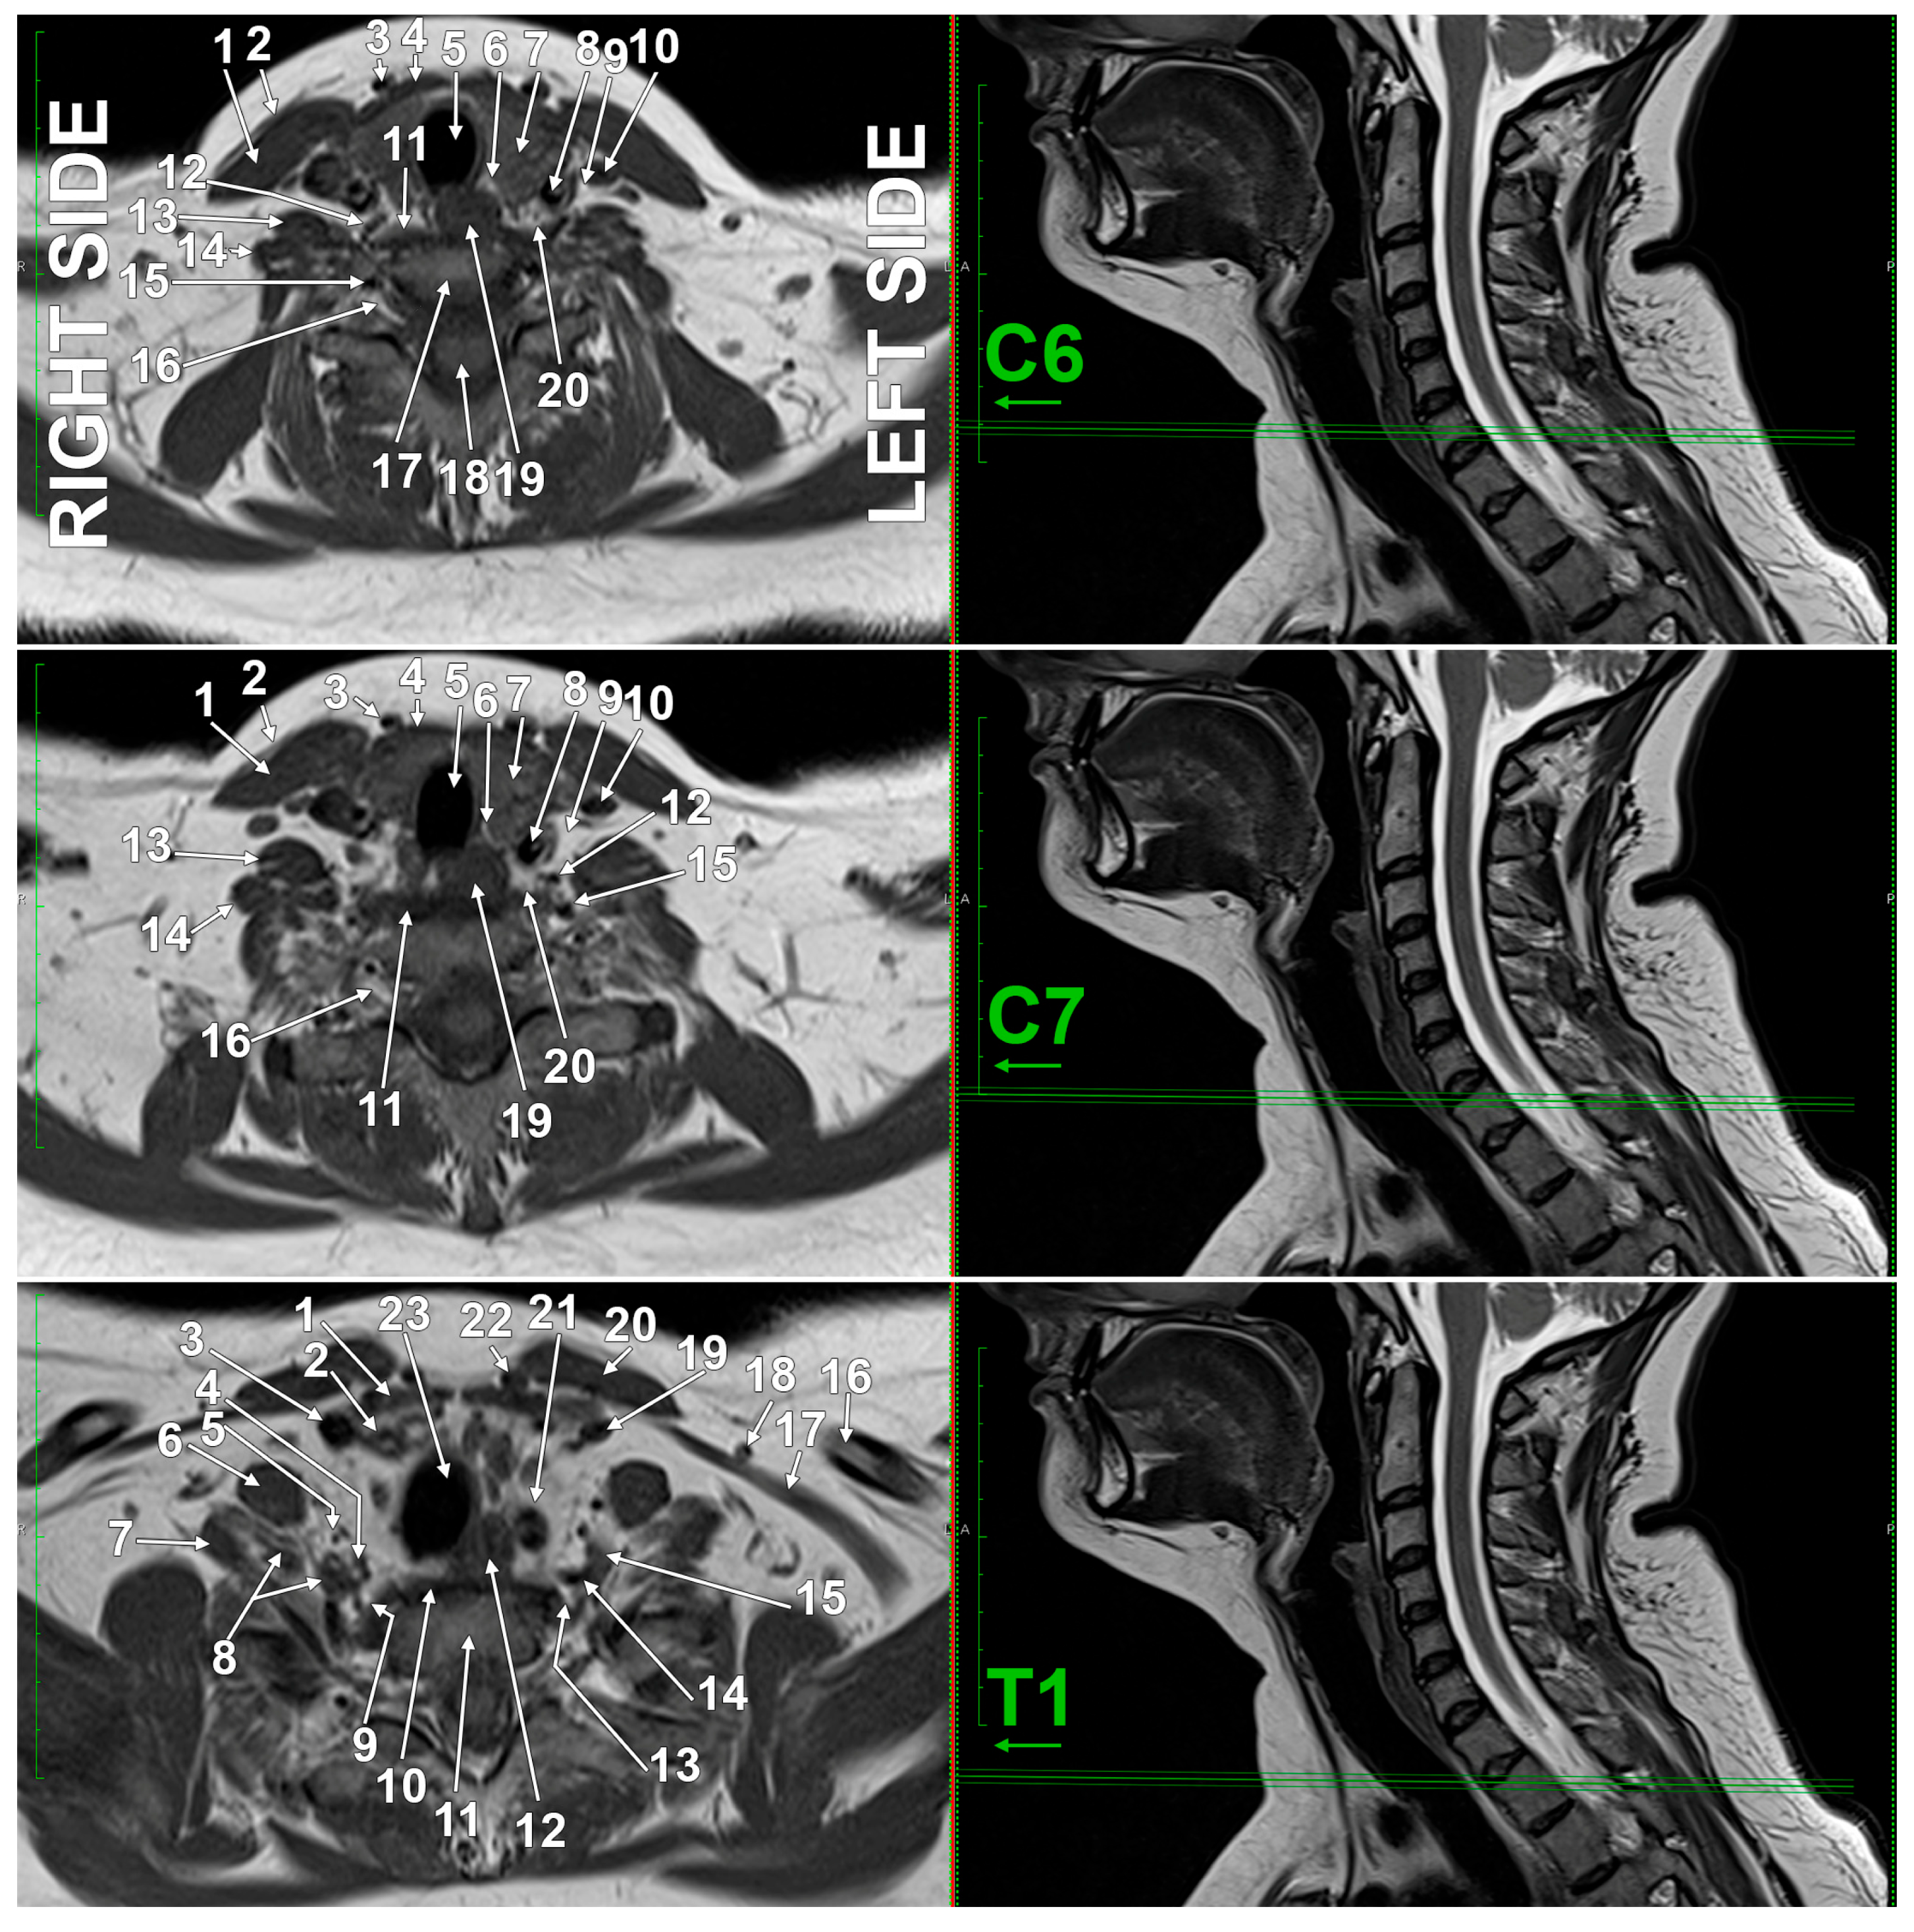

3.4. Imaging Anatomy of the SG